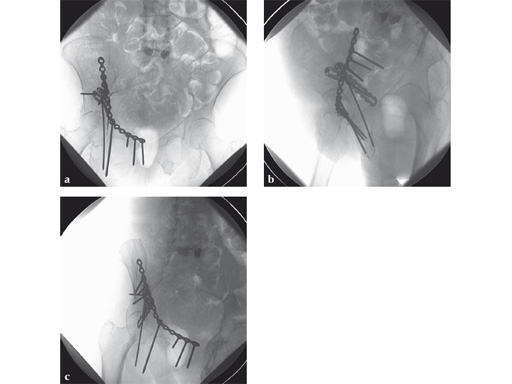

Fig 3ab AP hip and iliac oblique image intensifier views show initial quadrilateral surface plate placement with the aid of an asymmetrical clamp and subsequent introduction of overlying pelvic brim reconstruction plate. In this case a locking pelvic brim plate was chosen because of the severe osteoporosis.

Fig 4ac AP pelvis and Judet oblique x-rays 9 months postoperatively. The patient started full weight bearing at approximately 10 weeks postoperatively. The fractures healed without secondary displacement. The patient returned to preinjury (relatively limited) activity level with no significant residual pain complaints.